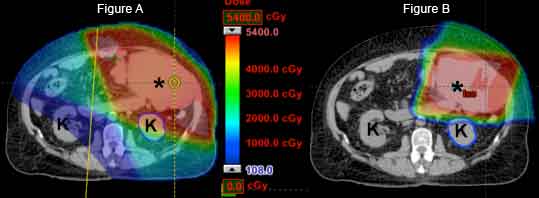

There is a growing emphasis on functional outcomes and quality of life in sarcoma patients. Proton therapy offers an innovative new approach to achieve these goals. As of 2020 there are 80 proton therapy centers in the world, including 35 centers in the United States – the University of Florida Health Proton Therapy Institute among them – fitted with the gantry systems necessary to address the diverse anatomical presentation of sarcoma. Due to unique physical characteristics of protons which cause them to stop within tissue, proton therapy can provide highly conformal radiation with minimal or no dose to normal organs. For instance, when a sarcoma is located in the abdomen or retroperitoneum, proton therapy may be utilized to save kidneys from the damaging effects of radiation. If the intestines can be avoided, there is less nausea during treatment.